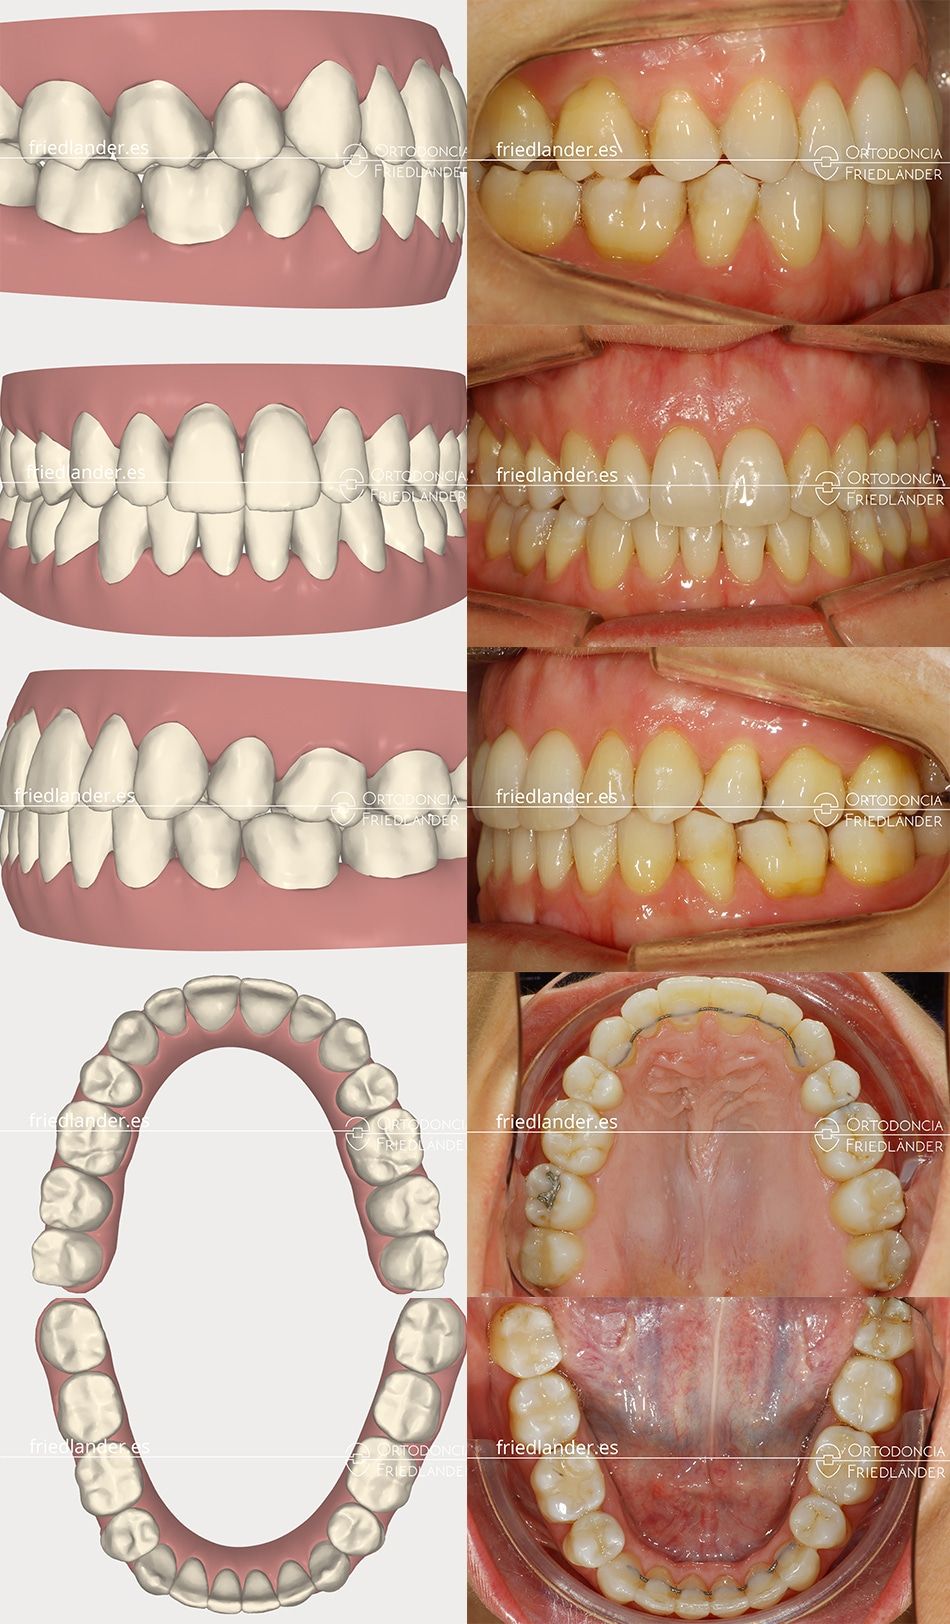

Imagen de la valoración del Clincheck y el resultado final del tratamiento. Es decir, la planificación virtual y el resultado real.